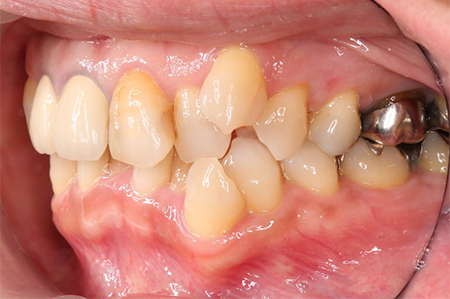

この患者様は長い事歯科医院には通っておらず、下の歯は前歯以外は全て崩壊していることが分かります。

前から見ても歯が欠けてしまい、歯茎も赤く腫れてしまっているのが分かります。

一般的には入れ歯が妥当かと思われますが、患者様は33歳、まだまだ人生は長いです。

奥歯がないと前歯でしか噛めなくなってしまい、残っている前歯もいずれダメになってしまいます。

また、奥歯がなくなってからの期間が長かったため、入れ歯が入るスペースが奥にないのが分かります。

様々なことを鑑み、患者様とも何度も話し合いを行い、下の奥歯には必要最低限のインプラントを、他の歯も外科処置を施しなるべく歯を抜かない方法を取りました。

最終的に抜歯した本数は下の歯5本。上の歯に関しては全て残すことが出来ました。

奥歯があることで前歯の負担を減らし、前歯を失うリスクを下げることが出来ます。